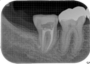

移植手術より2〜3週後より根管治療を行います(成人で根の成長が終了している患者さんの場合)。

根管治療の間隔は2〜3週毎で、約4ヶ月行います。

根管治療の終了後は、被せものをして、治療は終了となり、メインテナンスに移行して行きます。